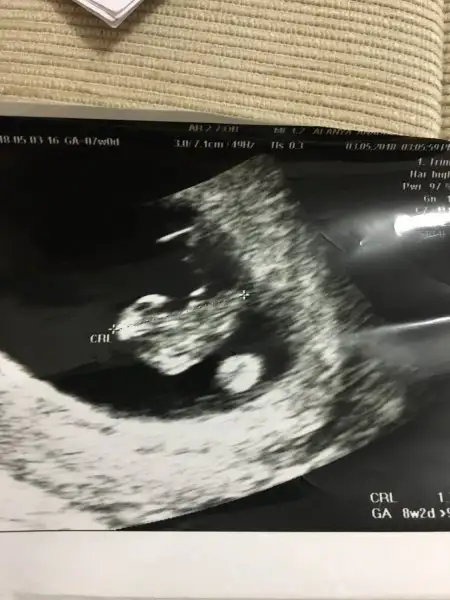

Canım ben yorum yapıcaktım ama plasentanın yerini tam belirleyemedim sağ da bir şey görüyorum sol taraftada o yüzdenKızlar bilen biri bana da yorum yapabilir mi acaba çok merak ediyorum en azından küçük bi yorum 7 haftalık karından ultrason

Kız cnm plasentayi net gördüm ama teori bu tabi tutar tutmaz7 haftalık karından sizce ne?

Ramzi teorisine göre ( bilimsel bir araştırma sonucuymuş ve %85 doğruluğu varmış). İlk 6-8 haftalık ultrason görüntüsüne göre bebeğin kesenin içersinde soldan ya da sağdan girişine göre cinsiyet tahmini yapılıyor. Bilimsel olunca tecrübeli annelerimiz yada anne adaylarımızdan yardım istiyoruz. Doğruluğu var mı öğrenmek adına :) Bizleri aydınlatırsanız çok seviniriz. bu teorieye göre;

Vajinal muayeneyle bakıldıysa eğer;

Sağdan girmiş gözüküyosa aslında solmuş ve ERKEK,

Soldan girmiş gözüküyosa aslında sağmış ve KIZ ,

Karından bakıldıysa eğer,

Soldan girmiş gözüküyosa gerçektede solmuş ve ERKEK,

Sağdan girmiş gözüküyosa gerçekte de sağmış ve KIZ,

o zaman bu teoriye göre kız oluyo canım onu bebek sandım ben :)